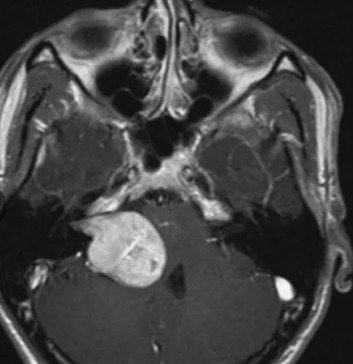

Невринома уха

Невринома уха 111 фотографий